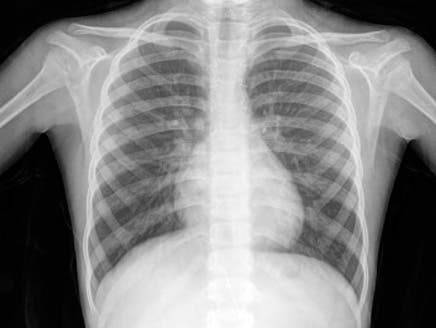

اخبارنا ــ اعتبر العميد الطبيب جعفر المومني، مستشار ورئيس اختصاص الأمراض الصدرية في الخدمات الطبية، أن وباء التبغ من أكبر الأخطار الصحية العمومية التي شهدها العالم على مرّ التاريخ.

وقال المومني إنه تُعد جميع أشكال التبغ ضارة، ولا يوجد مستوى آمن من التعرض للتبغ. ويظل تدخين السجائر النوع الأكثر شيوعًا لأنواع استخدام التبغ في كافة أنحاء العالم. وتشمل منتجات التبغ الأخرى تبغ النرجيلة، ومختلف منتجات التبغ العديم الدخان والسيجار والسيجاريليو والتبغ الجاهز للف باليد وتبغ الغليون ولفافات البيدي ولفافات الكريتيك.